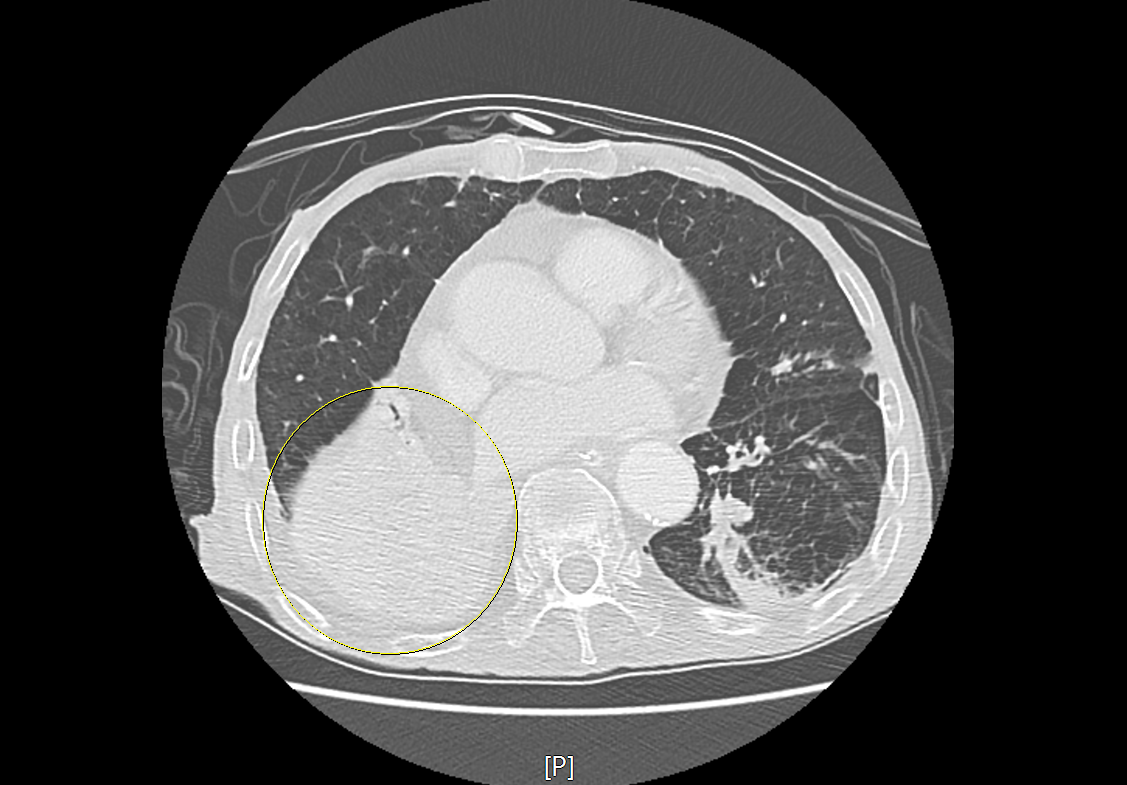

환자의 CT영상을 보시겠습니다.

위 CT영상을 보시면, 환자의 우측 기관지부터 공기 대신 음식물이 들어가 있는 모습을 볼 수있고, 그로 인해 폐실질에는 폐렴과 무기폐가 발생되어 있는 상황이었습니다.

이는 요양원에서 오는 환자분들에게서 흔히 보이는 폐렴의 형태로 흡인성 폐렴으로 생각할 수 있습니다.